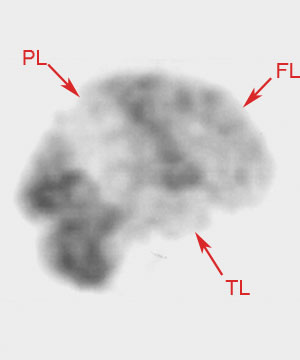

FDG PET reveals temporoparietal metabolic deficits in patients with Alzheimer's disease. Although asymmetry is not uncommon, usually certain brain structures show metabolic sparing including the basal ganglia, thalamus, cerebellum, and primary sensorimotor cortex. Finally, on SPECT imaging bilateral temporoparietal hypoperfusion as well as decreased uptake in the medial temporal lobes and cingulated regions may be exhibited. |

![]() ![]() Both images above are SPECT images using Tc-99 in an individual with severe Alzheimer's disease. |